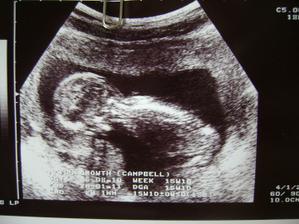

@zuzulaxx🙂 hm...dobrá otázka🙂bola som umelo oplodnená.odo dna vkladu embrií po prvé sono(fotka)sú to 4 týždne,doktor mi ale povedal že som v 5 týždni,ale od poslednej menštruácie je to 7 týždnov....takže som z toho úplne mimo🙂)))))))))))))Vidím,že sme na tom podobne🙂))))))))))))gratulujem🙂